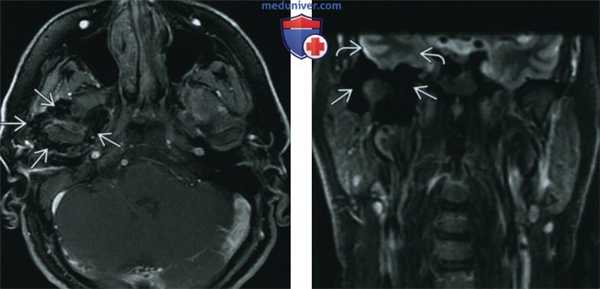

(Слева) При MPT T1BИ FS с КУ в аксиальной проекции, выполненной пациенту с пигментным ворсинчато-узелковым синовитом (ПВУС), в расширенном суставном пространстве правого ВНЧС и вокруг него визуализируются многочисленные узлы с гипоинтенсивным сигналом. Обратите внимание, что контрстаное усиление выражено минимально.

(Справа) При корональной МРТ в режиме STIR у пациента, страдающего ПВУС, вокруг головки мыщелка нижней челюсти справа визуализируются узлы с гипоинтенсивным сигналом. Обратите внимание на «засвечивание» (блюминг-артефакт) основания черепа, обусловленное включением гемосидерина в узлах, и являющееся практически патогномоничным признаком.

(Справа) При МРТ Т1ВИ в корональной проекции визуализируется гипоинтенсивное объемное образование правого ВНЧС с «ободком» низкой сигнальной интенсивноаи. Также визуализируется гипоинтенсивное экстрааксиальное объемное образование в средней черепной ямке, тесно прилежащее к интракраниальным структурам, с таким же гипоинтенсивным «ободком» по периферии. (Слева) При MPT T1BИ FS с КУ в аксиальной проекции, выполненной пациенту с пигментным ворсинчато-узелковым синовитом (ПВУС), в расширенном суставном пространстве правого ВНЧС и вокруг него визуализируются многочисленные узлы с гипоинтенсивным сигналом. Обратите внимание, что контрстаное усиление выражено минимально.

(Слева) На аксиальной МРТ (Т2 ВИ) на уровне дна средней черепной ямки над областью правого ВНЧС визуализируется объемное образование с сигналом очень низкой интенсивности обусловленное распространением пигментного ворсинчато-узлового синовита из ВНЧС в полость черепа.

(Справа) На аксиальной МРТ (Т1 ВИ C+FS) у этого же пациента определяется легкое контрастное усиление солидных участков объемного образования у пациента с пигментным ворсинчато-узловым синовитом.